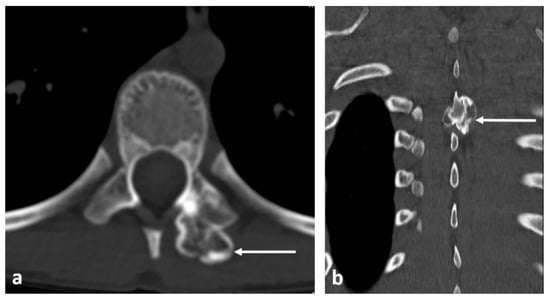

3.3. Osteoblastoma

- Galgano, M.A.; Goulart, C.R.; Iwenofu, H.; Chin, L.S.; Lavelle, W.; Mendel, E. Osteoblastomas of the spine: A comprehensive review. Neurosurg. Focus 2016, 41, E4. [Google Scholar] [CrossRef]

| Osteoblastoma | Expansile lucent lesion. Sclerotic rim. Bone destruction. Variable intralesional ossification. | Low to intermediate T1 signal and intermediate to high T2 signal. Surrounding soft tissue oedema, extra osseous soft tissue component. |